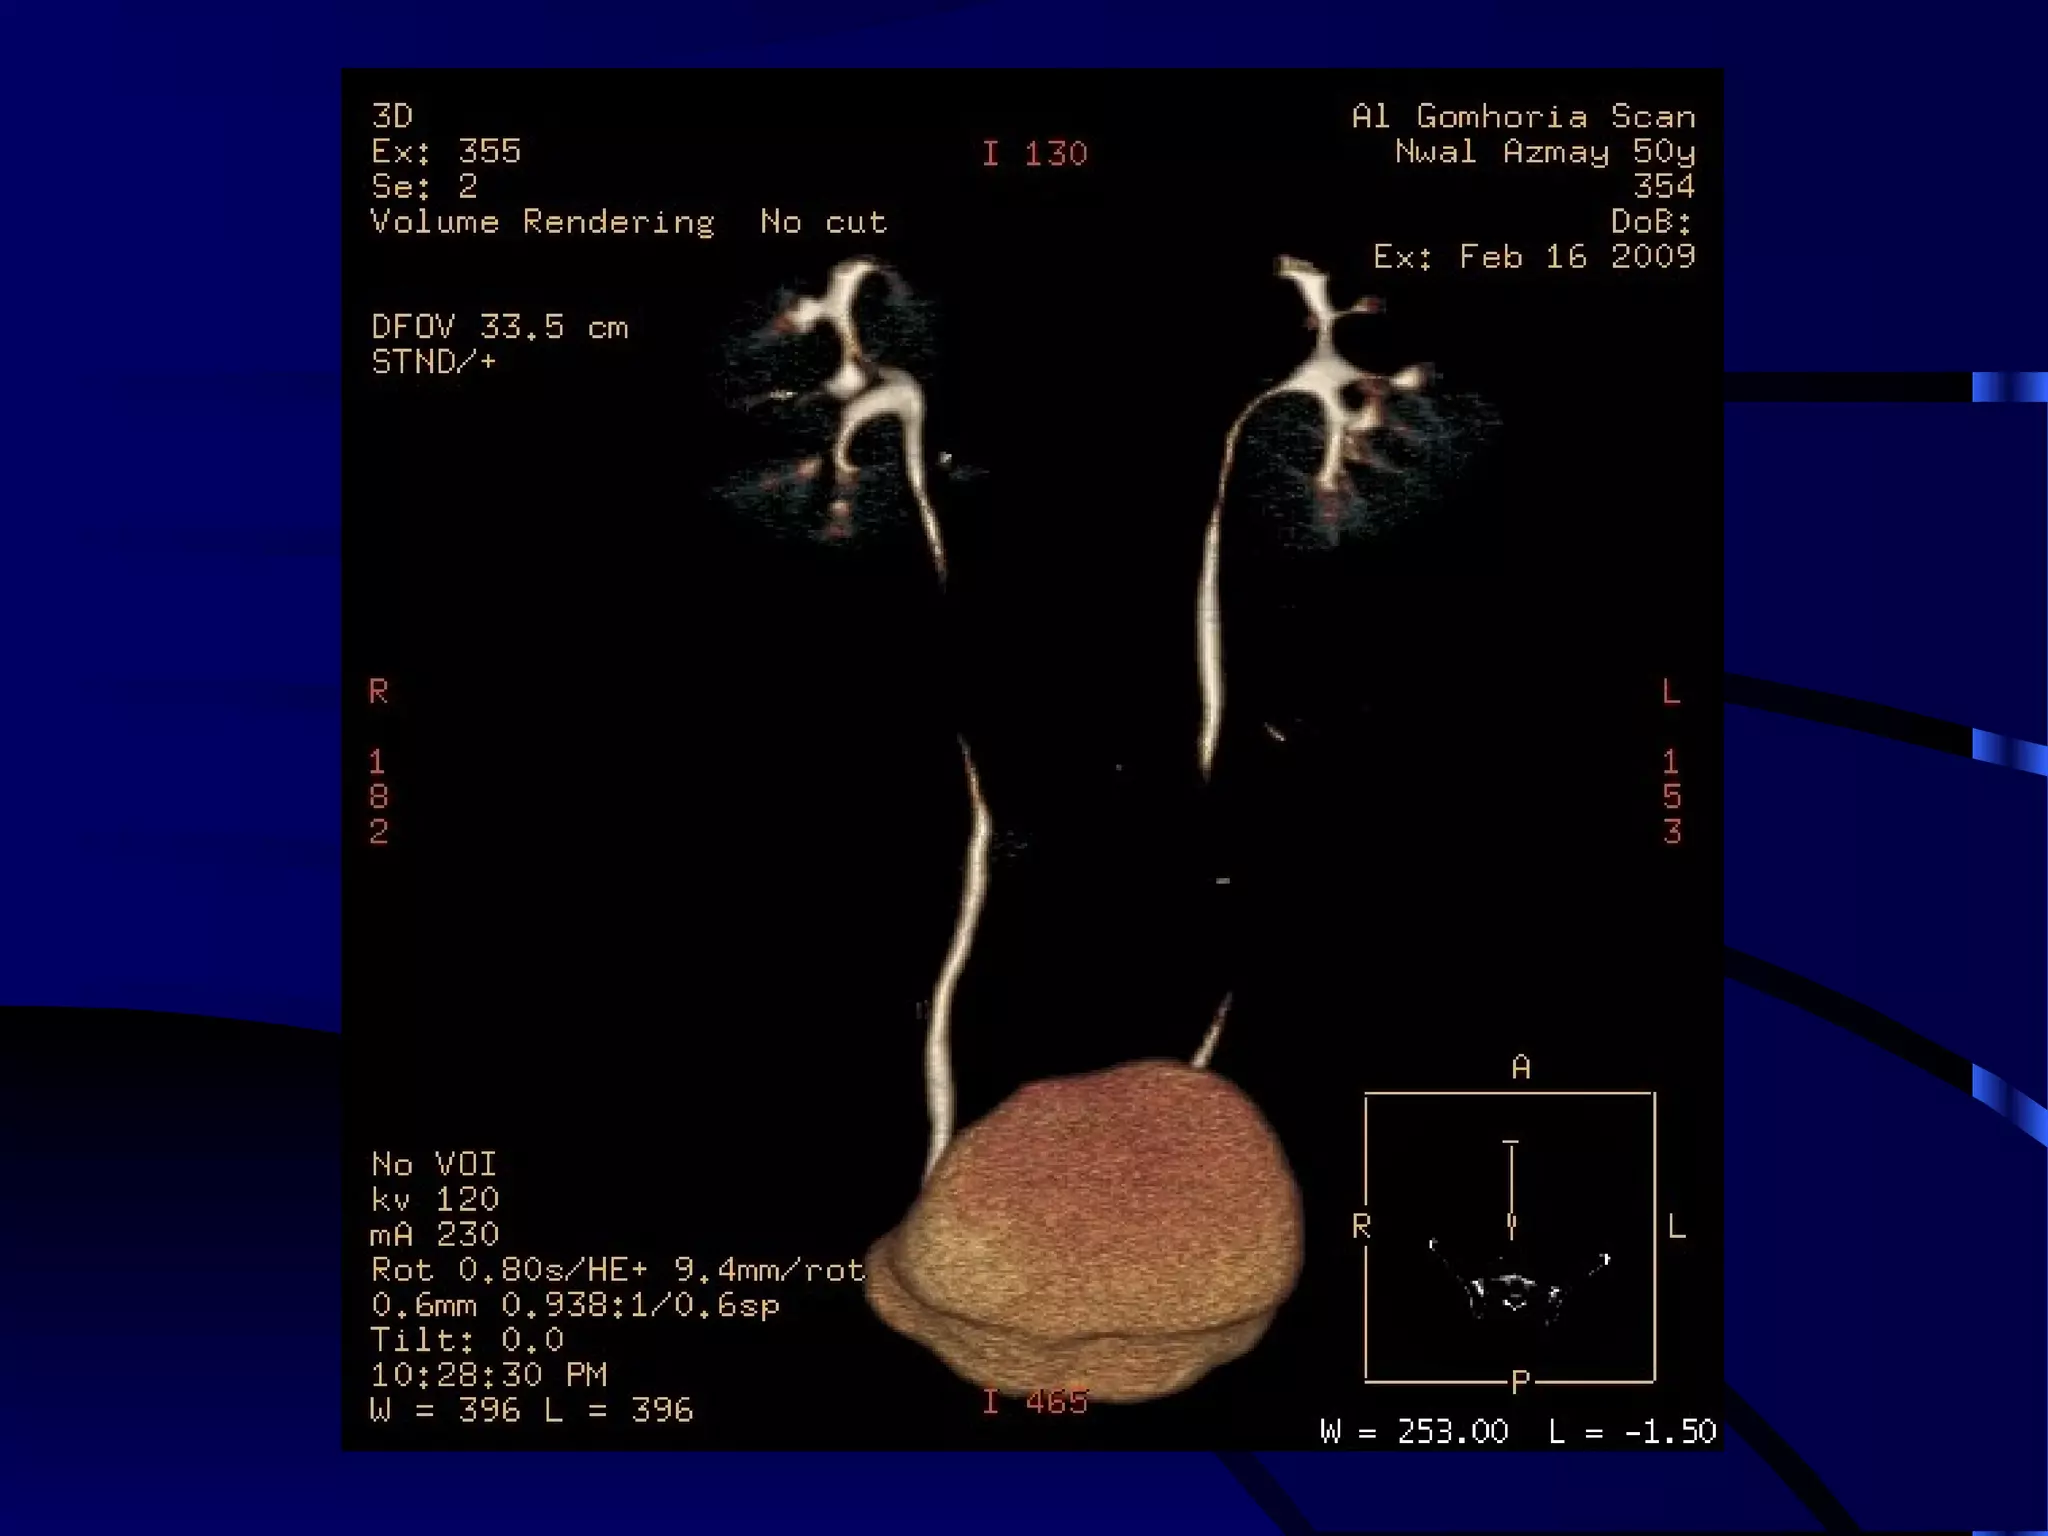

MALIGNANT LOWER POLAR LEFT RENAL MASS WITH

ENHANCING MALIGNANT THROMBUS WITHIN THE IVC

AND SECONDARY VARICOSITIES OF THE LEFT TESTICULAR VEIN.